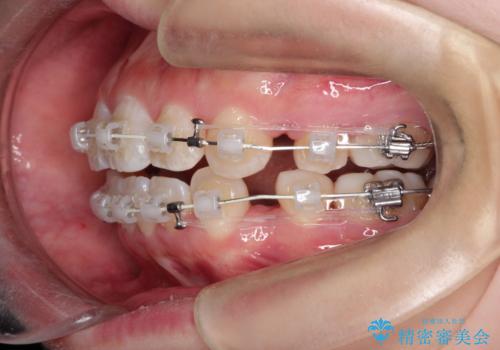

- 矯正装置

- 審美装置

- 治療計画

- ”口元を下げたい”が主訴で来院されました。

抜歯してワイヤー矯正を行い、口元も改善され大変満足していただきました。

小臼歯の抜歯を行うことで口元を改善することができました。